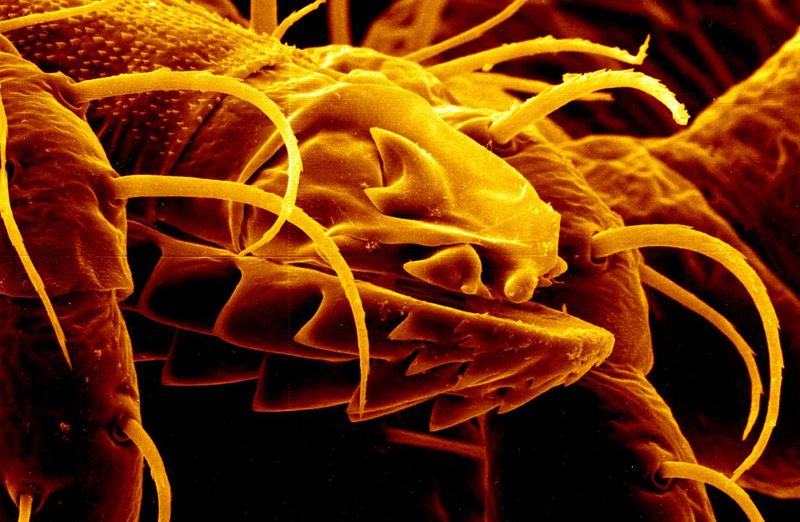

E-cigarettes and vapes work by producing an aerosol by heating a liquid that contains nicotine, marijuana, or other drug products as well as added chemicals and flavorings which can contain harmful products like heavy metals, cancer-causing chemicals, and other volatile organic compounds. The CDC notes that e-cigarettes have the potential to benefit some people, like those aiming to quit smoking, but may harm others. Scientists are still studying the products to understand risks and possible benefits, but advise that they should never be used by youth, young adults, or pregnant women.